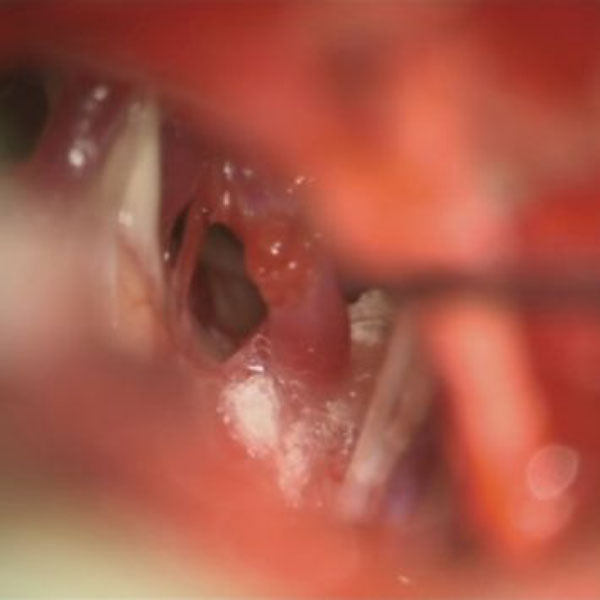

減圧前

減圧後